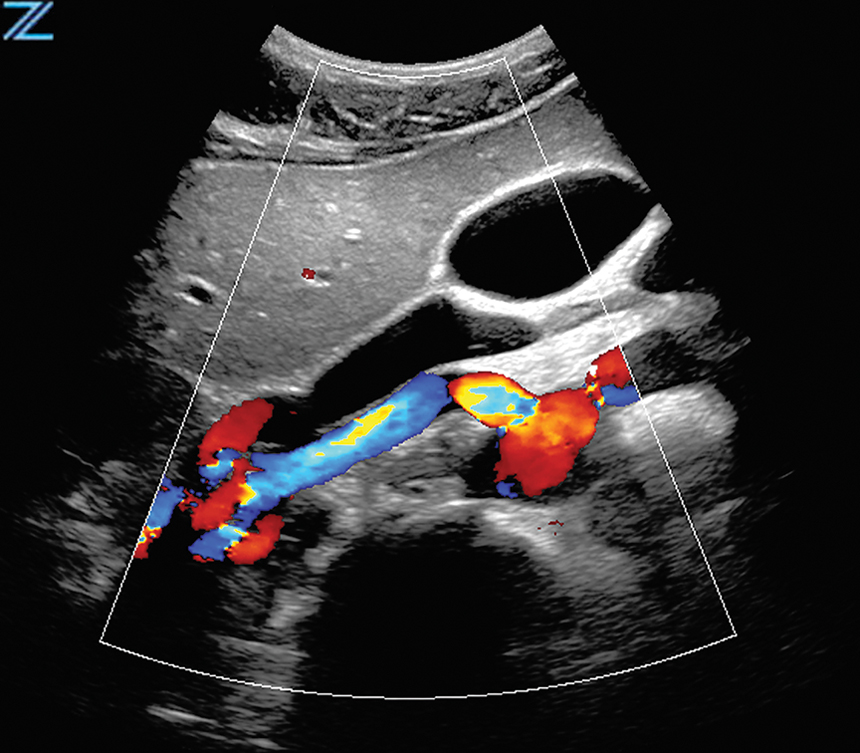

Renal Perfusion | SC8-3